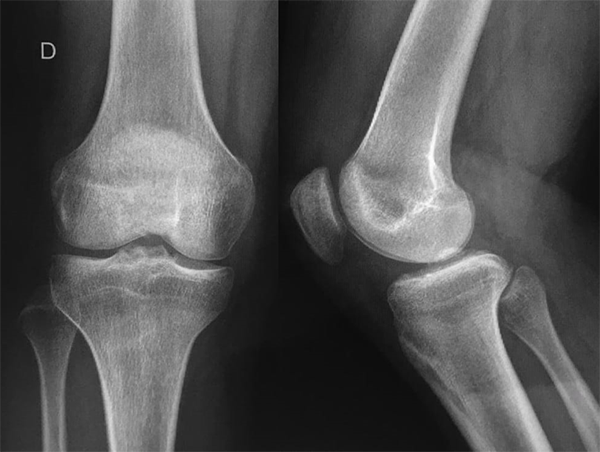

Se solicitó Rx, donde se constató fractura de espina tibial grado 3 (fig. 1), además, una tomografía axial computada (fig. 2), aportando un patrón conminuto del fragmento y RM, donde se evidenció, además de la fractura de espina tibial, una lesión en asa de balde del menisco interno (fig. 3).

Figura 1: Radiografía de rodilla derecha frente y perfil. Nótese el déficit de extensión en el frente y la fractura avulsión de espina tibial en ambas proyecciones.

Al año postoperatorio presenta una rodilla fría, seca, estable, Lachman y Pivot negativos, con rango de movilidad 0-125°. En los scores funcionales: Lysholm, 97 puntos y Tegner, 7. Se solicitó Rx de control en la que se evidenció consolidación de la fractura (fig. 9).

Figura 9: Rx control de rodilla derecha. Un año postoperatorio. Signos de consolidación completa de la fractura de espina tibial.